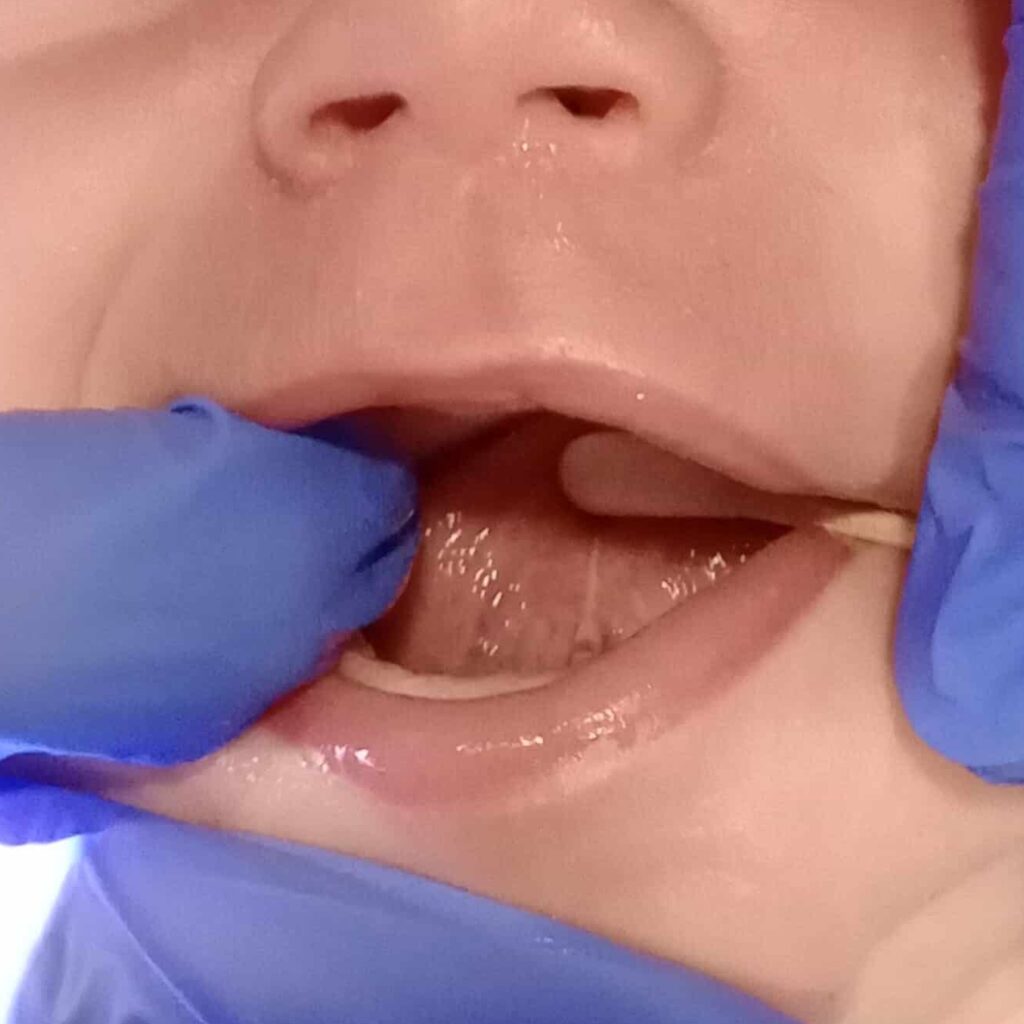

Pre surgery lip tie

Pre Lip Tie Surgery